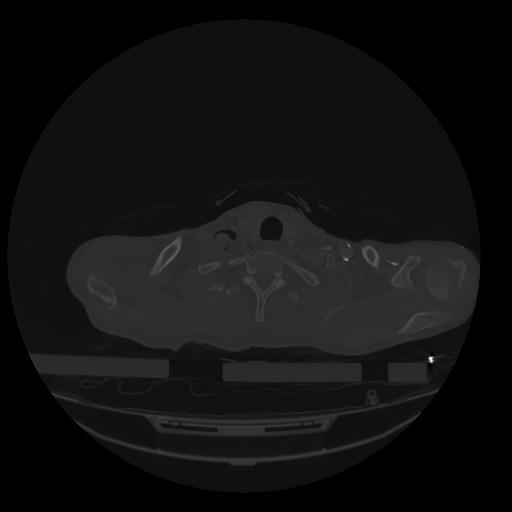

28 CUERPO,CE,Vol,2.0,CUERPO,,